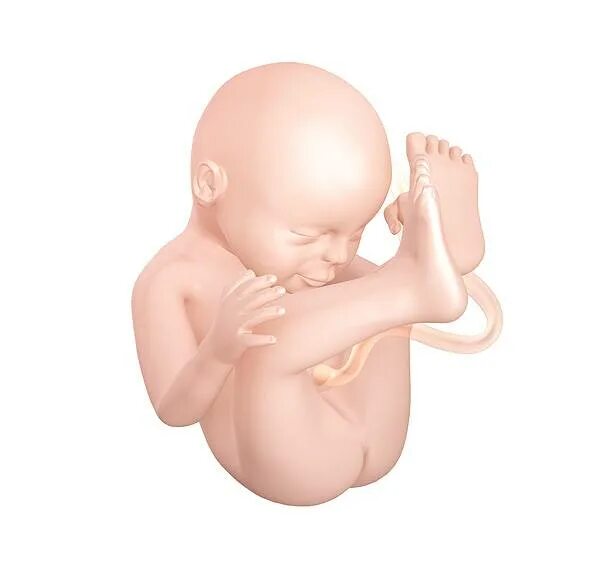

Плод на 31 неделе беременности. ребенок в животе 31 неделя.Эмбрион 31 неделя беременности. малыш на 31 неделе беременности.Плод на 31 неделе беременности. эмбрион 31 неделя беременности. малыш в утробе 31 неделя беременности.Малыш на 31 неделе беременности. малыш в животике 28 недель. малыш в утробе 31 неделя.Младенец в утробе. малыш в утробе 31 неделя. ребёнок на 31 неделе беременности.Плод на 31 неделе беременности. ребёнок на 31 неделе беременности. малыш в утробе 31 неделя. младенец на 31 неделе беременности.Плод на 31 неделе беременности. 30-31 неделя беременности. эмбрион 31 неделя беременности. 31 акушерская неделя беременности.Малыш на 31 неделе беременности.Плод на 31 неделе беременности. расположение ребёнка в утробе матери на 29 неделе.30-31 неделя беременности. ребёнок в матке на 31 неделе. плод на 31 неделе беременности.Плод ребенка. ребёнок на 31 неделе беременности.Плод на 31 неделе беременности. малыш в утробе 31 неделя беременности. ребёнок в 30 недель беременности. ркбкеок на 30 неделе беременности.Плод на 31 неделе беременности. малыш на 31 неделе беременности.Эмбрион леннарт нильсон. плод на 31 неделе беременности. леннарт нильсон фотографии.Малыш на 31 неделе беременности. ребёнок на 31 неделе беременности в животе. малыш в утробе 31 неделя беременности.Узи плода 31 неделя беременности. узи беременности 30-31 неделя. узи 31 неделя беременности мальчик. 31 неделя беременности узи фото.Узи на 33 неделе беременности мальчик. снимок узи на 31 неделе беременности. узи 31 неделя беременности мальчик.Плод на 31 неделе беременности. расположение ребенка в утробе матери на 30 недели беременности. расположение плода на 31 неделе беременности. малыш в утробе матери 31 неделя беременности.Узи плода 31 неделя беременности. 31 неделя беременности фото узи ребенка. снимок узи на 31 неделе беременности. узи беременности 30-31 неделя.Плод на 31 неделе беременности. 31 неделя беременности фото плода. плод ребенка в 31 неделю беременности. малыш на 31 неделе беременности.Плод на 30 неделе беременности. плод ребенка на 30 неделе беременности. ребёнок в 30 недель беременности. 31 неделя беременности фото плода.31 неделя беременности как выглядит31 неделя беременности фото плода на узи. 3д узи 31 неделя беременности девочка. 3д узи на 31 неделе беременности.Узи 31 неделя беременности. узи плода 31 неделя беременности. 31 неделя беременности узи фото. эмбрион на 30 неделе беременности узи.Ребёнок на 31 неделе беременности. узи хомиладорлик.Узи ребенка на 31 неделе беременности. 32 недели беременности фото плода на узи. 31 неделя беременности фото плода на узи. снимок узи 32 недели беременности.Малыш в животике на 32 неделе. ребёнок на 31 неделе беременности. 31-32 неделя беременности.Живот на 31 неделе беременности. животик на 31 неделе беременности. ребёнок на 31 неделе беременности в животе.Живот на 31 неделе. животик на 31 неделе беременности. беременный живот на 31 неделе.Беременность 29 недель положение плода. ребенок в животе на 25 неделе. плод на 32 неделе беременности. матка на 21 неделе беременности.Малыш в утробе 32 неделе беременности. плод 31-32 недели беременности. ребёнок на 32 неделе беременности в утробе. плод в 32 недели беременности в животе.Живот на 31 неделе. живот на 30-31 неделе. живот на 31 неделе беременности животик.Ребёнок на 24 неделе беременности. оебнок на 24 неделе беременности. новорожденный ребенок на 24 неделе беременности.Ребёнок 30 неделя беременности в утробе. малыш в утробе 31 неделя беременности.Ребенок в 32-33 недели беременности. плод на 33 неделе беременности. ребенок на 33 неделе беременности. малыш на 33 неделе беременности.Ребёнок в 34 недели беременности в утробе. 32 недели беременности фото плода. малыш в утробе 32 неделе беременности. ребёнок в 32 недели беременности в животе.Ребёнок на 32 неделе беременности. новорожденный в 35 недель.Малыш на 31 неделе беременности. новорожденный ребенок 31 неделя. рождение ребенка на 31 недели беременности.31 неделя беременности как выглядитПлод на 34 неделе беременности картинки. 34 неделя беременности фото плода. 34 эмбриональная неделя беременности. плод ребенка в 34 недели беременности.